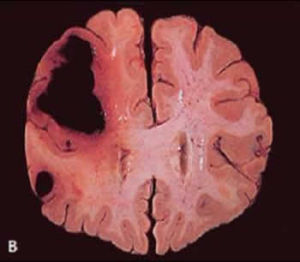

also mistaken for a drug lead to exacerbation of also mistaken for a drug lead to exacerbation of . 2. According to clinical manifestations, especially neuroimaging evidence: (1) of the massive cerebral infarction is usually the internal carotid artery, middle cerebral artery or cortical branch of the complete stroke, Expressional focus is on the side of the complete hemiplegia unilateral sensory disturbance and contralateral to the lesion of gaze palsy

vertebro - basilar artery infarction visible disturbance of consciousness, and the majority of cranial nerve paralysis, progressive obvious signs of cerebral edema and increased intracranial pressure, brain herniation, the severity of the illness,There are potentially life - threatening vertebro - basilar artery infarction visible disturbance of consciousness, and the majority of cranial nerve paralysis, progressive obvious signs of cerebral edema and increased intracranial pressure, brain herniation, the severity of the illness,There are potentially life - threatening . (2) cerebral watershed infarction (CWSI) is adjacent to the blood supply to the boundary at the watershed, or ischemia, also referred to as edge band (2) cerebral watershed infarction (CWSI) is adjacent to the blood supply to the boundary at the watershed, or ischemia, also referred to as edge band .

multi - cerebral infarction due to hemodynamic disturbance, typically occurs in internal carotid artery (ICA) severe stenosis or occlusion of organs such as blood pressure lowering or they may be derived from cardiac or arterial embolic source multi - cerebral infarction due to hemodynamic disturbance, typically occurs in internal carotid artery (ICA) severe stenosis or occlusion of organs such as blood pressure lowering or they may be derived from cardiac or arterial embolic source . (3) of hemorrhagic cerebral infarction is a focal cerebral infarct and necrosis of the artery so that blood leakage or hemorrhage, common in large cerebral infarction after (3) of hemorrhagic cerebral infarction is a focal cerebral infarct and necrosis of the artery so that blood leakage or hemorrhage, common in large cerebral infarction after .

(4) multiple cerebral infarction is two or more different cerebrovascular blood - supply system while the occlusion of the cerebral infarction.